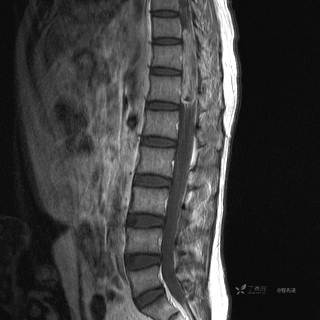

MR

T1增强